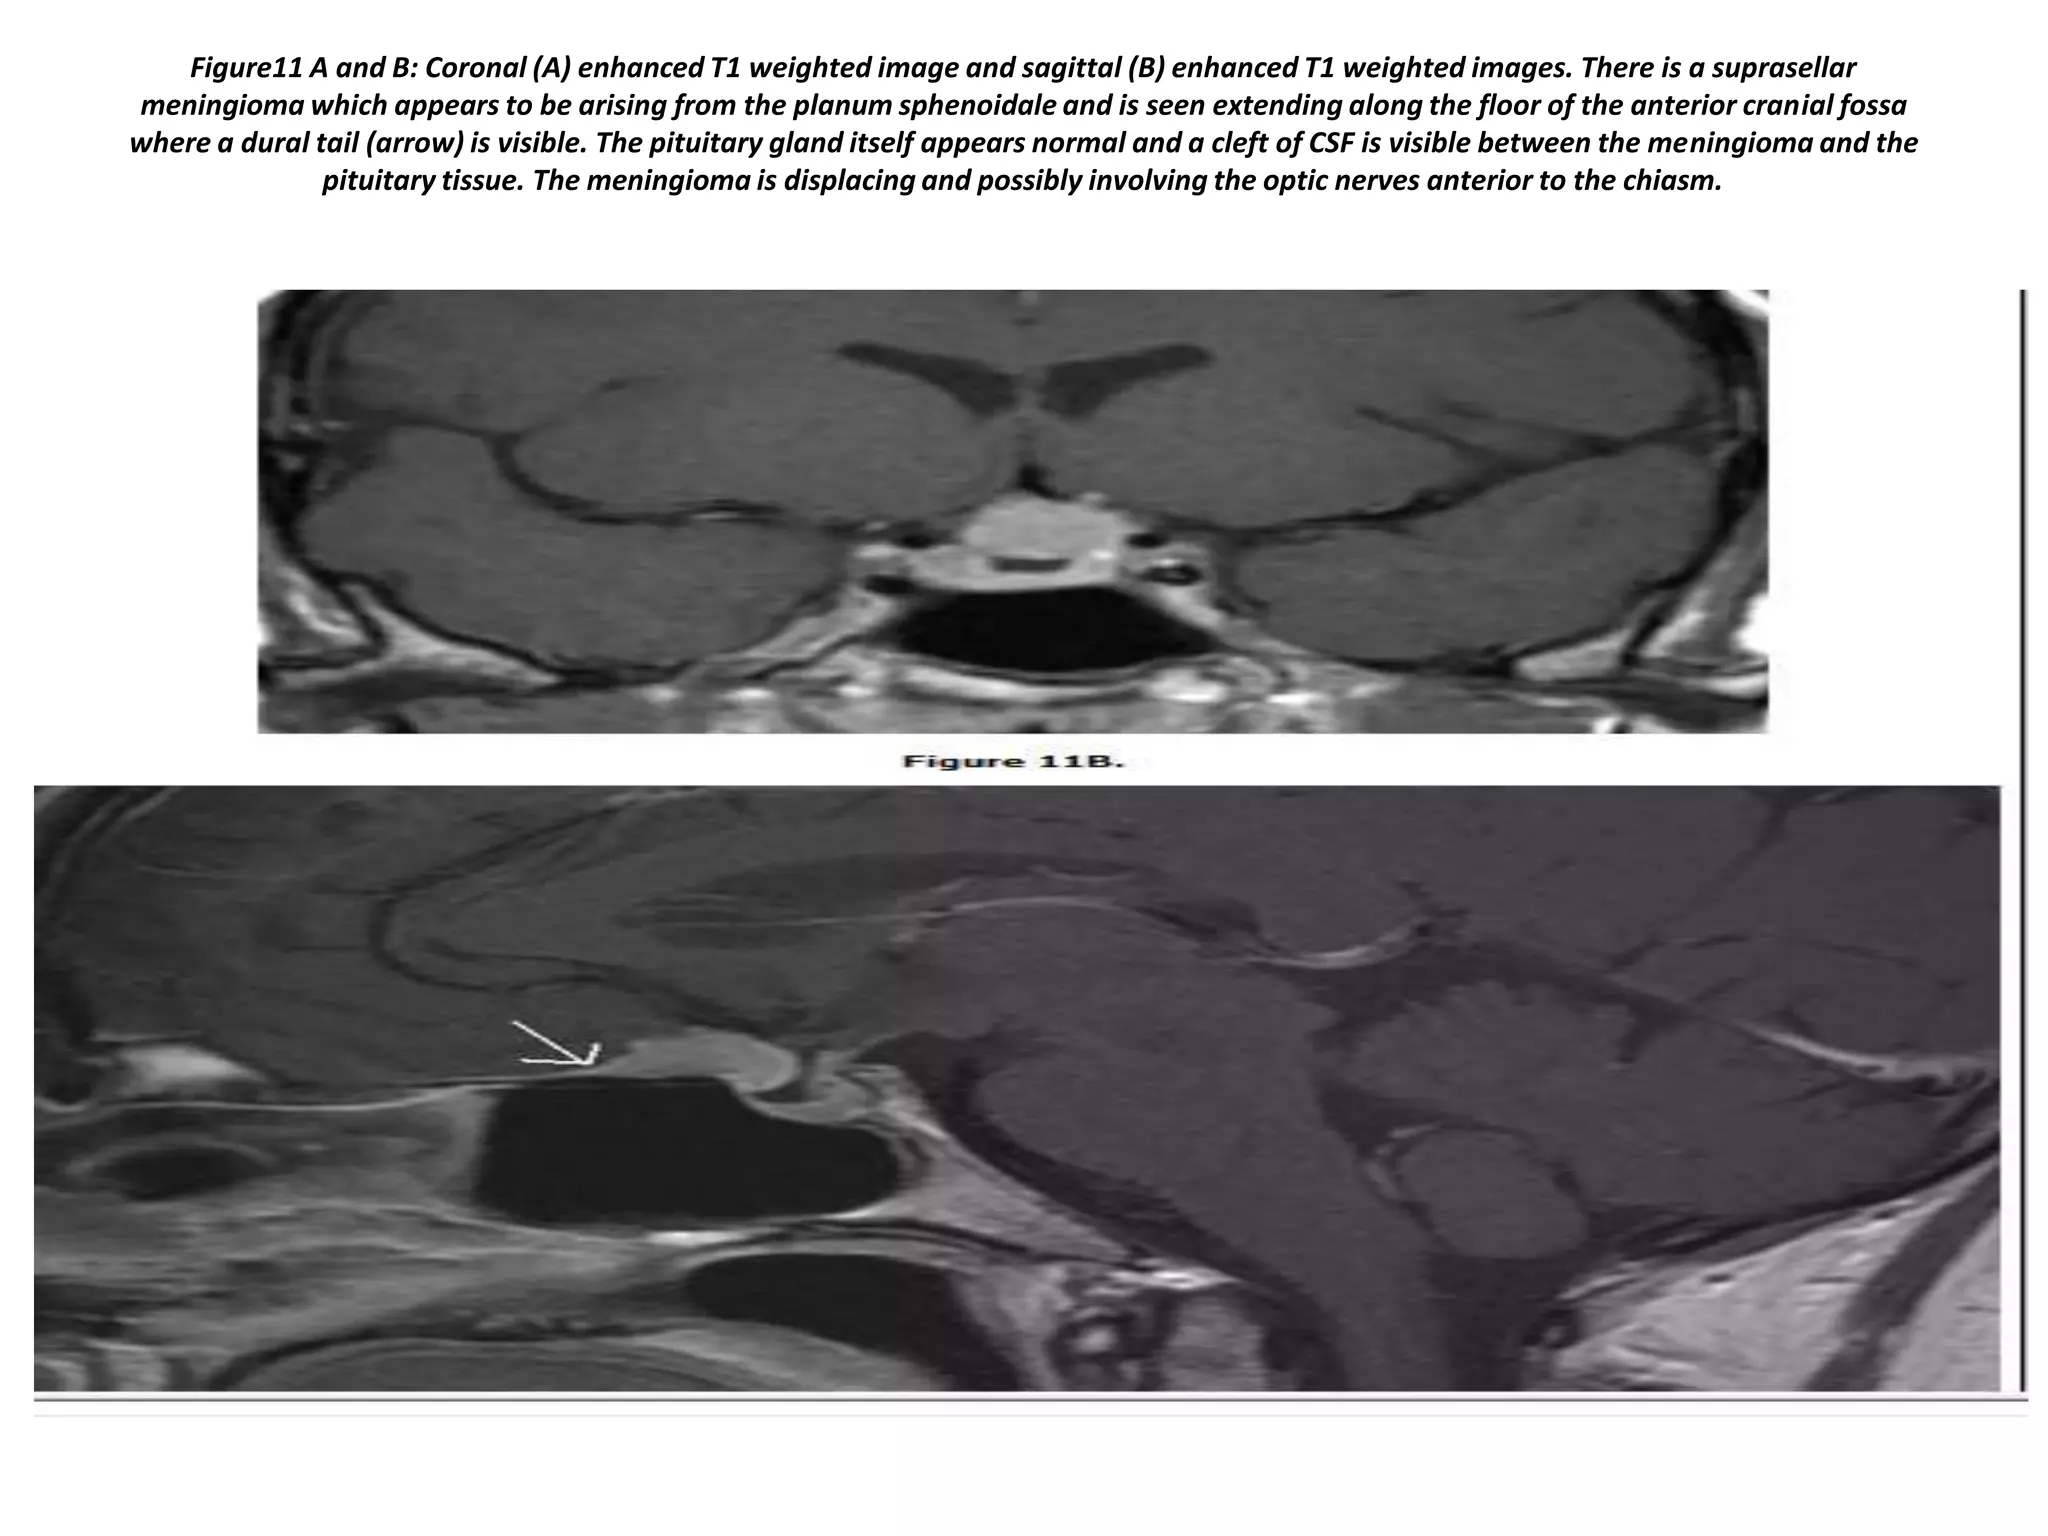

Figure11 A and B: Coronal (A) enhanced T1 weighted image and sagittal (B) enhanced T1 weighted images. There is a suprasellar

meningioma which appears to be arising from the planum sphenoidale and is seen extending along the floor of the anterior cranial fossa

where a dural tail (arrow) is visible. The pituitary gland itself appears normal and a cleft of CSF is visible between the meningioma and the

pituitary tissue. The meningioma is displacing and possibly involving the optic nerves anterior to the chiasm.